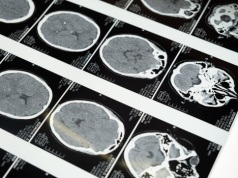

Analiza przeprowadzona przez lekarza ze Środkowego Zachodu USA Historia w skrócie Demencja typu Alzheimera jest jednym z najważniejszych wyzwań medycznych, przed którymi stoi nasz kraj (m.in. stanowi niewiarygodne obciążenie dla społeczeństwa, np. w zeszłym roku oszacowano, że kosztowała Stany Zjedn...